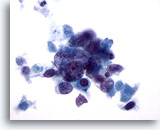

画像 4

肺FNA、肺腺癌

波状縁を呈する悪性腺細胞の集塊。背景には何も見られず、腫瘍性背景を呈していません。悪性細胞の保存状態は良好です。細胞質には、離散性の空胞が微細なものから大きなものまで見られ、一部には取り込まれている好中球が認められます。 60倍

画像 4

肺FNA、肺腺癌

波状縁を呈する悪性腺細胞の集塊。背景には何も見られず、腫瘍性背景を呈していません。悪性細胞の保存状態は良好です。細胞質には、離散性の空胞が微細なものから大きなものまで見られ、一部には取り込まれている好中球が認められます。

60倍